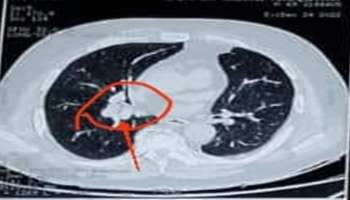

நுரையீரலில் சிக்கிய சோள துண்டுகள் - வெற்றிகரமாக வெளியே எடுத்த ரேலா மருத்துவமனை

சென்னை மகிந்திரா வேர்ல்டு சிட்டியைச் சேர்ந்த 55 வயதான நபர் ஒருவர் சோளத்தை படுத்துக் கொண்டே சாப்பிட்டதால் அது அவரது மூச்சுக் குழாய் வழியாக சென்று நுரையீரலில் சிக்கிக் கொண்டது.